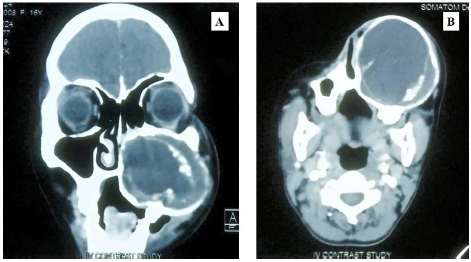

Background: Retained ballistic foreign bodies in anatomically intricate regions such as the nasopharynx or paranasal sinuses are exceptionally rare and pose diagnostic and therapeutic challenges.

Cases: We present two cases in 49-year-old males: Case 1 involved a bullet lodged in the posterior nasopharyngeal wall with multiple tooth fragments embedded in the tongue following intraoral gunshot trauma; Case 2 featured a metallic fragment retained in the left posterior ethmoid sinus after a self-inflicted nasal gunshot wound.

Management and Outcome: Both patients underwent emergency surgical intervention—open retrieval and tracheostomy for Case 1, endoscopic sinus surgery with septoplasty for Case 2—and recovered uneventfully.

Conclusion: These cases underscore the critical role of high resolution computed tomography, multidisciplinary planning, and tailored surgical approaches in successfully managing rare upper aerodigestive ballistic injuries.